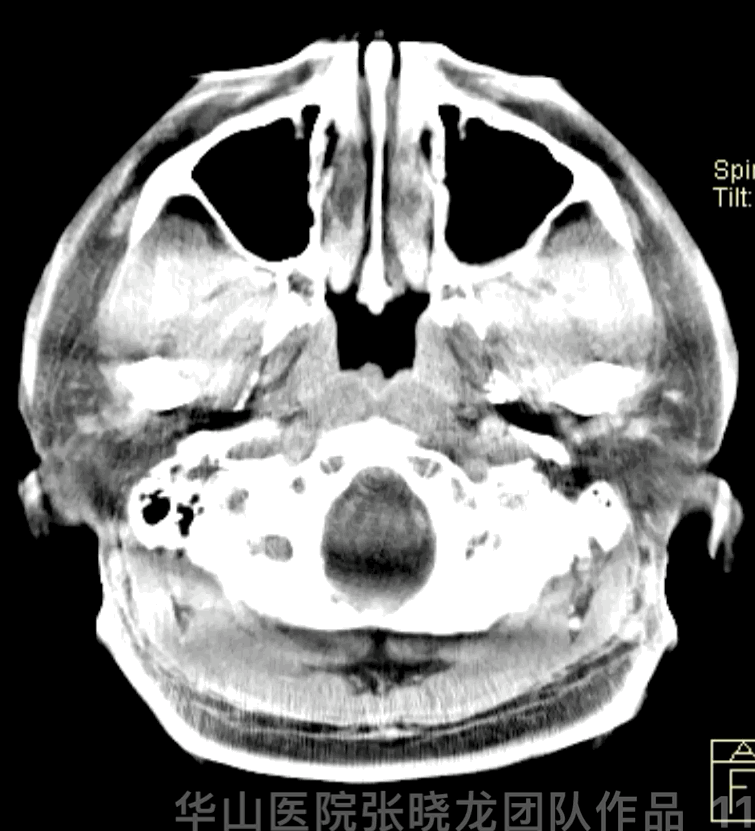

Figure 11 GIF. No hemorrhage was observed from Dyna-CT.

图 11 GIF. Dyna-CT未见出血。